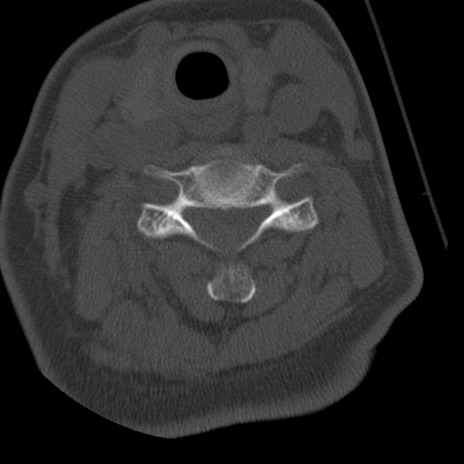

症例50 頚椎CT(横断像)

頚椎CT